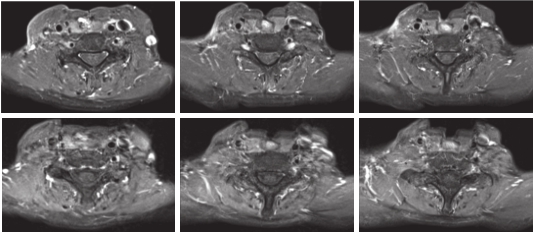

2019-02-18—2019-04-05行术后放疗(因身体情况差未行同步化疗):IMRT PGTV=70Gy/35F,PGTVtb=66Gy/33F,PCTV=60Gy/33F,放疗后继续口服安罗替尼维持治疗1年。

疗效评估:患者口服安罗替尼1周期后疗效评估达PR(图3),术后放疗后疗效为CR,随访至今,病情维持CR状态,局部MRI及全身检查未见肿瘤复发转移,无病生存时间已达30个月以上(图4)。

图4 放疗结束后(2019-04-04)及随访复查(2021-06-23),疗效为CR